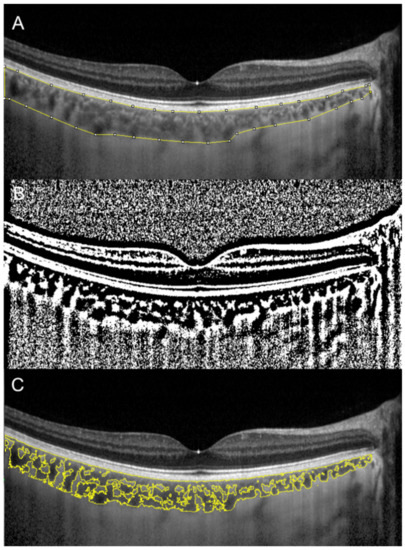

CVI was also investigated in eyes with geographic atrophy (GA) [59]. In the latter study, 34 patients with GA and 32 control subjects were retrospectively analyzed. The CVI was found to be reduced in patients with GA and it continued to reduce during the follow-up period (Figure 4). These results may suggest a stromal replacement of the choroidal vessels occurring in the setting of GA [59].

Figure 4. Choroidal vascularity index calculated with the OCT image binarization algorithm in a patient with geographic atrophy (A) and in an age-matched healthy subject (B) was 61.3% and 65.2%, respectively.